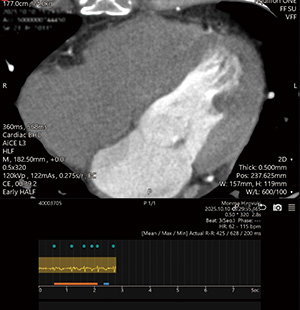

セグメント再構成

b

1ビートによるハーフ再構成

c

CLEAR Motionを使用

図2 心房細動

アブレーション術前肺静脈造影CT。心拍コントロールせず、複数ビート撮影。セグメント再構成(a)ではモーションアーチファクトが目立つが、1ビートによるハーフ再構成(b)にCLEAR Motionを使用することで、モーションアーチファクトの少ない画像が取得できた(c)。左房の評価目的であったが冠動脈の評価も可能となった。